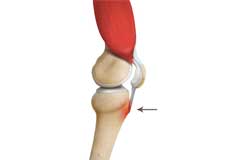

Osgood-Schlatter disease refers to a condition in older children and teenagers caused by excessive stress to the patellar tendon (located below the kneecap). Participants in sports such as soccer, gymnastics, basketball, and distance running are at higher risk for this disease.

Osgood Schlatter Disease